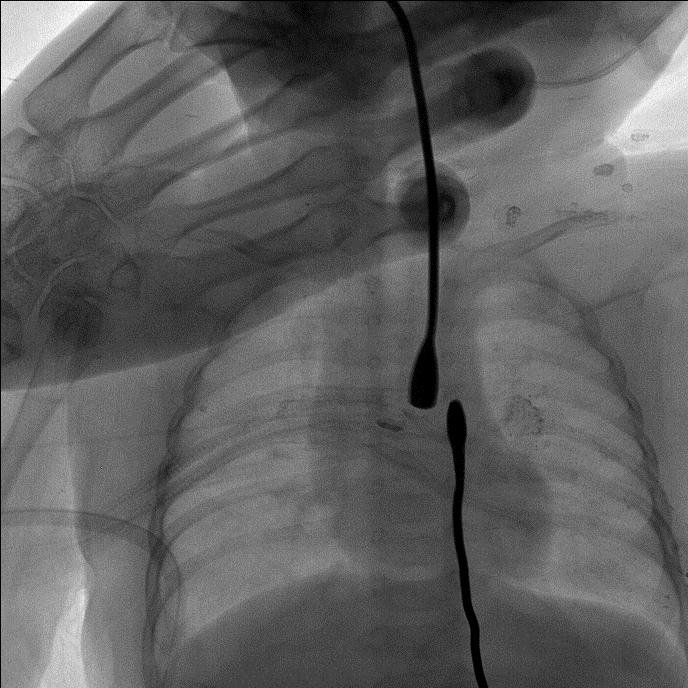

近日,在上海交通大学医学院附属新华医院(以下简称“新华医院”),儿普外科专家为小仁仁进行了食道重建手术,在小小的胸部仅打了3个5mm的小孔,将原本是个“死胡同”的食道,成功地“解锁”了。

先天性食道闭锁是新生儿期严重消化道畸形,食道上下没有相连,一旦喂奶,将全部进入肺部,如不手术,患儿将在很短的时间内因营养不良和肺炎双重打击迅速死亡。胸腔镜下食管闭锁手术被称为新生儿外科手术领域皇冠上的明珠,总体治疗难度高,是国际上公认的体现新生儿外科总体水平的标志性疾病。而仁仁所患的食道闭锁I型又是其中最罕见、最严重的一种。他的食管近远端距离约达4.8cm,属于长段缺失型食管闭锁。由于仁仁年龄小,手术难度极大,当地医院就先为仁仁做了胃造瘘手术。手术后经胃造瘘喂养。于是,贡噶曲则抱着仁仁辗转成都等地,开始了千里求医之路。经病友介绍,贡噶曲则通过互联网找到了新华医院儿普外科主任王俊。

“患儿手术时只有5公斤多一点,微创操作本身视野小,新生儿组织结构脆弱,所以对操作精细度要求很高。”新华医院儿普外科主任王俊介绍,尽管手术难度大,但胸腔镜微创的手术方案,避免了传统开胸手术带来的巨大创伤和后遗症,更利于仁仁的恢复。除了外科手术,先天性食道闭锁治疗其实更是一个多学科联合诊治的过程。

“比如食道闭锁的孩子往往在气道方面也会有一些问题,所以要早发现,进行一些功能上的训练。”王俊说,像仁仁这样的孩子因为食道闭锁没法吃东西,新生儿天生的吸吮反射几周后就会消失,“到时候他就不会吞咽了,所以说孩子一到医院我们就给他做了一个吞咽反射的训练。”此外,还要定期对仁仁进行食道内应力延长,让食道近远端距离尽早符合手术条件。最终,在多学科的保驾护航下,王俊在细若棉线的食道上穿针引线,完成食管重建。整个手术仅耗时1小时40分钟,手术出血仅为2ml。